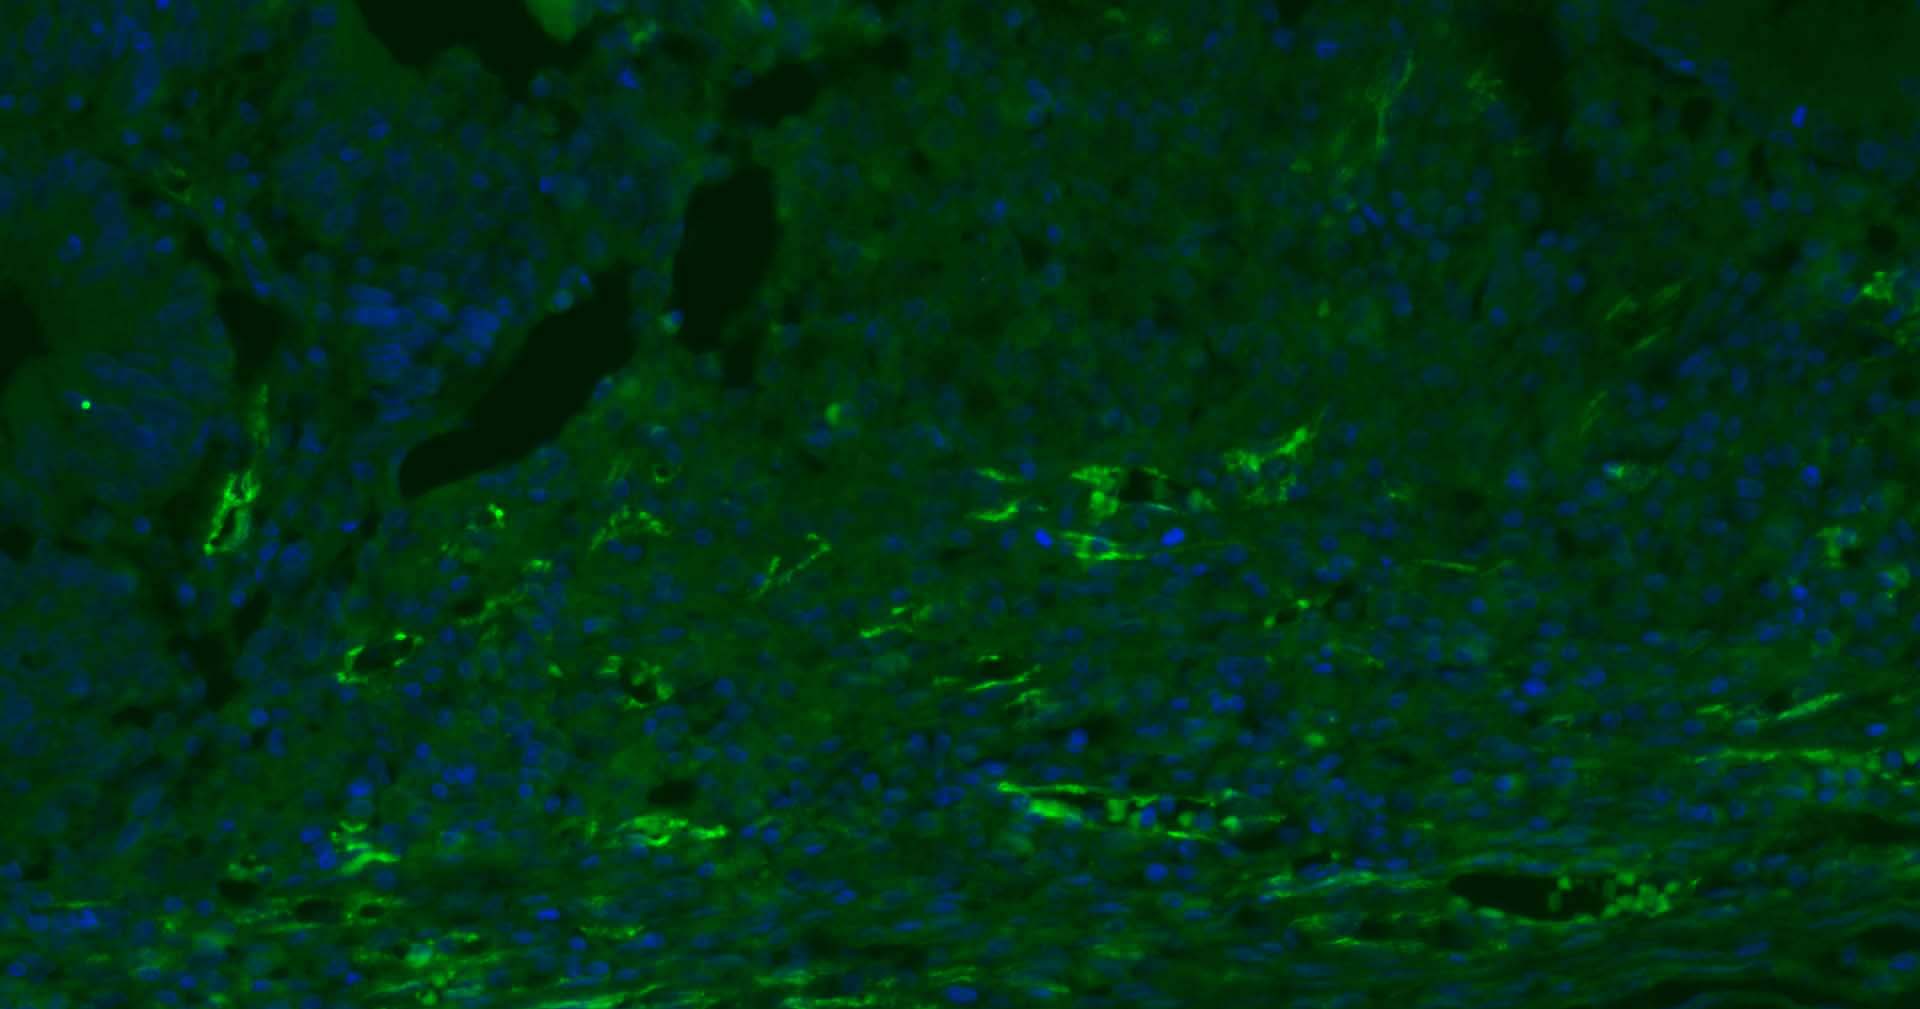

| IF | Human | 1:200-2000 | |

Expressed on platelets and leukocytes and is primarily concentrated at the borders between endothelial cells (PubMed:18388311, PubMed:21464369).

Expressed in human umbilical vein endothelial cells (HUVECs) (at protein level) (PubMed:19342684, PubMed:17580308).

Cell adhesion molecule which is required for leukocyte transendothelial migration (TEM) under most inflammatory conditions (PubMed:19342684, PubMed:17580308).

Tyr-690 plays a critical role in TEM and is required for efficient trafficking of PECAM1 to and from the lateral border recycling compartment (LBRC) and is also essential for the LBRC membrane to be targeted around migrating leukocytes (PubMed:19342684).